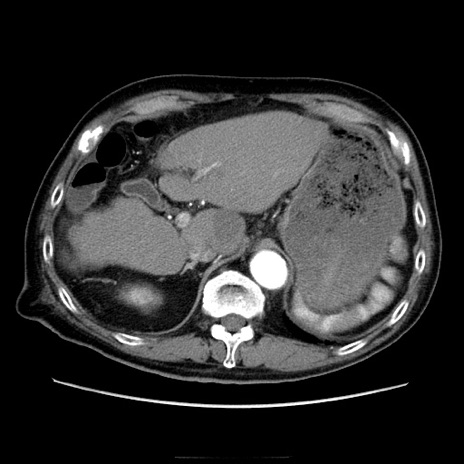

症例21(横断像)

【症例】70歳代男性

【主訴】腹痛

【現病歴】肝硬変・肝細胞癌にてかかりつけの方。約9時間前に食後より腹痛出現。症状が徐々に増悪し、嘔吐出現したため来院。

【既往歴】肝硬変、肝細胞癌(RFA、TACE後)

【身体所見】意識清明、表情苦悶様、BT 36℃、BP 129/78mmHg、P 88bpm、SpO2 97%(RA)、右上腹部から心窩部にかけて圧痛あり、反跳痛なし、筋性防御あり。

【データ】WBC 5800、CRP 0.16